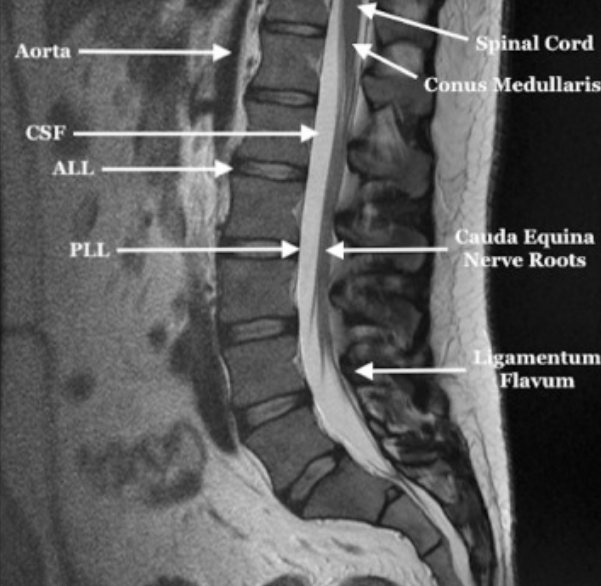

Image Type Lumbar Spine X-Ray CT Scan MRI Scan Anteroposterior (AP) Canal Diameter Cauda Equina Nerve Root Area Conus Medullaris Level Cross-Sectional Area (CSA) of Spinal Canal Disc-Height Index (DHI) Disc Herniation Size Disc Herniation Types Dural Sac CSA Epidural Fat Thickness Filum Terminale Thickness Foraminal Height and Width High-intensity Zone (HIZ) Lateral Recess Width/Depth Modic Endplate Changes (Type I, II, III) Modic (Marrow Signal) Changes Pfirrmann Classification (I-V) Vertebral Bone Quality (VBQ) Score Vertebral Endplate Defects